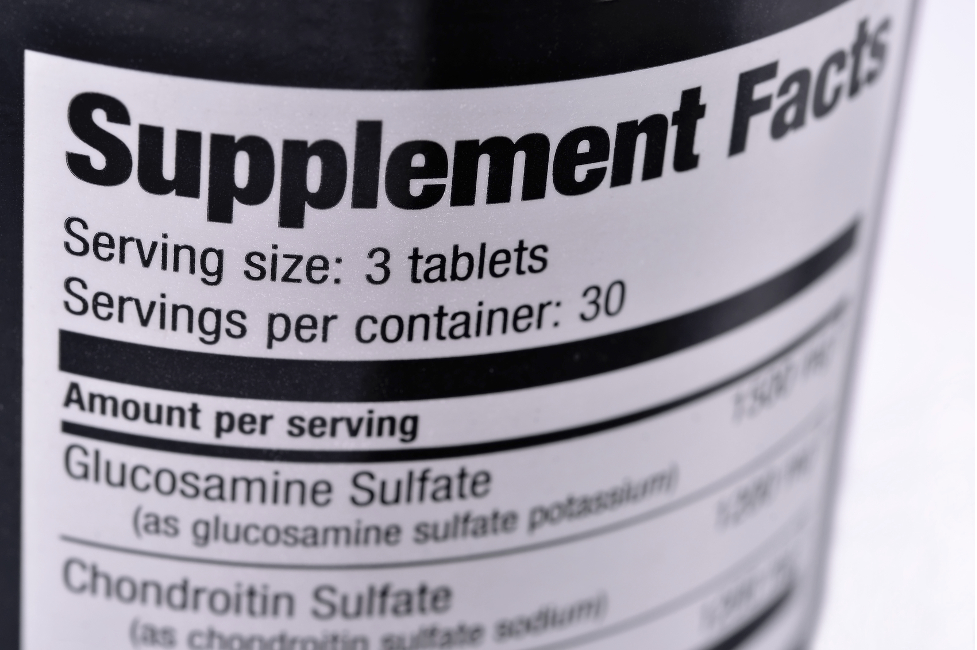

The answer to your question is YES. Many nutritional supplements have been proven to provide relief from joint pain, stiffness, and other arthritis symptoms. Some of the natural products being studied for Osteoarthritis (OA) and rheumatoid arthritis (RA) include Glucosamine and chondroitin, oleic acid, SAM-e, and curcumin. When used in conjunction with traditional treatments, some of these natural remedies may help relieve arthritis symptoms.

Some of the most popular arthritis supplements and how they work can be found below.